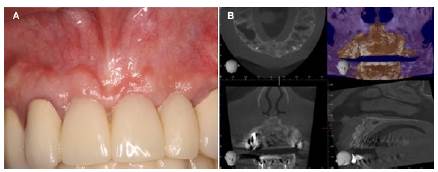

Posteriormente, se realizó la colocación de fibrina rica en plaquetas, hueso tipo Lumina Bone Porous Lumina Coat dentro de los alveolos (Figura 3 A,B). Finalmente, se suturó y se dio espera a la evolución del paciente (Figura 3C). Se prescribió amoxicilina 825 mg + ácido clavulánico 125 mg por 7 días, Meloxican 15 mg al día acetaminofén 325 mg + codeína 30mg por 7 días.

Después de 6 meses se observó la cicatrización completa de la zona, la encía de color normal, sin hinchazón ni signos de inflamación. Los datos radiológicos mostraron una mejoría en la apariencia radiográfica, con eliminación de los procesos inflamatorios óseos. Por tal motivo, se procedió a colocar una prótesis adhesiva tipo Maryland cementada con resinas desde el día 8, posterior a la cirugía de manera provisional para mantener la estética de la paciente (Figura 4A). Luego de 12 meses post-quirúrgico, se realizó otra tomografía axial computarizada que reveló la gran cantidad de hueso regenerado en la zona tratada (Figura 4B).